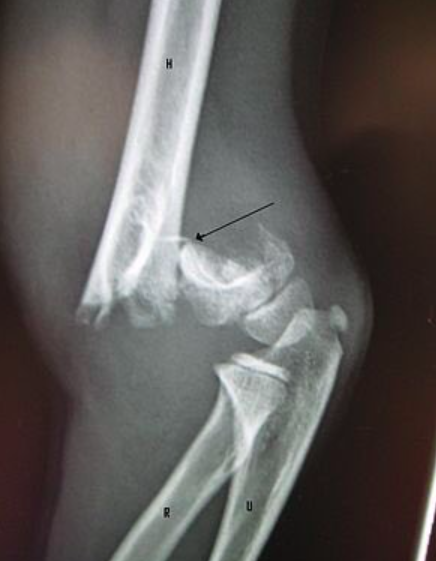

كسور الأطفال